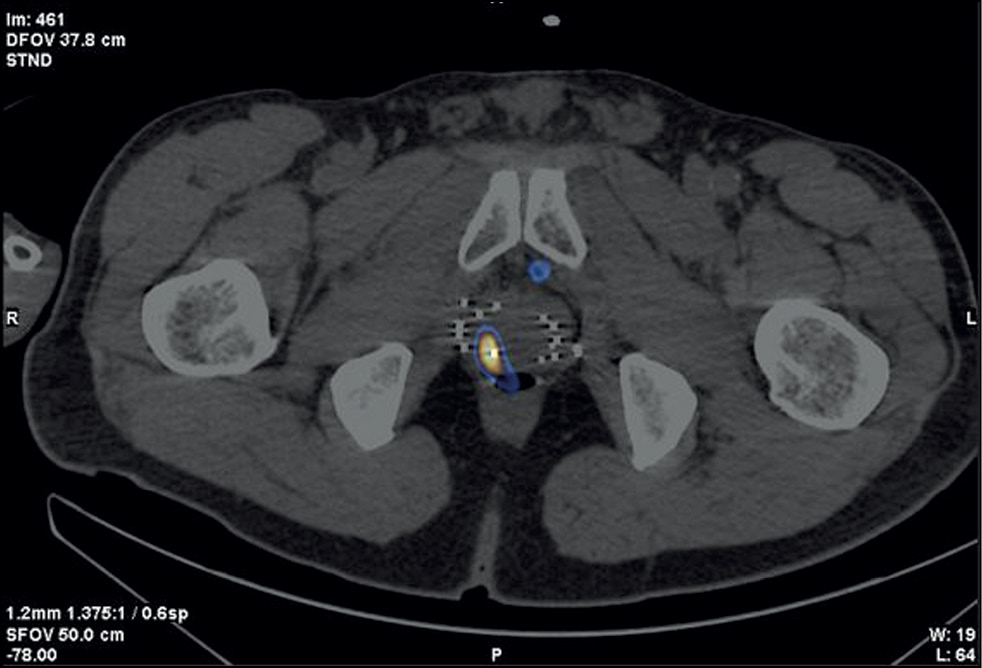

Figure 1 shows an example of pre-implantation brachytherapy planning using 125I sources. Crosses indicate virtual holes in the stereotactic array, which fully corresponds to the array implanted in a patient. Red dots indicate microsources, whereas colored lines indicate isodose distribution.

Fig. 1. Stages of dosimetry planning of brachytherapy localized prostate cancer using 125I microsources considering SPECT/CT with 99mTc-HYNIC-PSMA: (a) topometric marking and (b) topometric marking and dosimetry planning of brachytherapy.